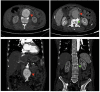

A 67-year-old man with diabetes and hypertension presented with complaints of abdominal pain and lower back ache for 7 months, with intermittent episodes of fever. On examination, there was an expansile mass in the upper abdomen with bruit on auscultation. He also had tenderness in the L1-L2 vertebral space with paraspinal fullness, causing painful restriction of lower limb motor functions but without affecting sensation. On evaluation, he was found to have an abdominal aortic aneurysm with infective lumbar spondylodiscitis. The aspirate from the paravertebral infected tissue and cultures from blood grew Pseudomonas aeruginosa, a rare causative agent of mycotic aortic aneurysm. Whether the infective spondylitis spread to the abdominal aorta causing the mycotic aneurysm or vice versa is a dilemma in such a case. However, the mainstay of treatment remains adequate source control and repair of the aneurysm with appropriate antibiotic therapy. Our patient received intravenous antibiotics for P . aeruginosa based on sensitivity, following which he underwent debridement of the infective spondylodiscitis with aneurysmorrhaphy. He had an uneventful recovery and was well at 3-month follow-up.